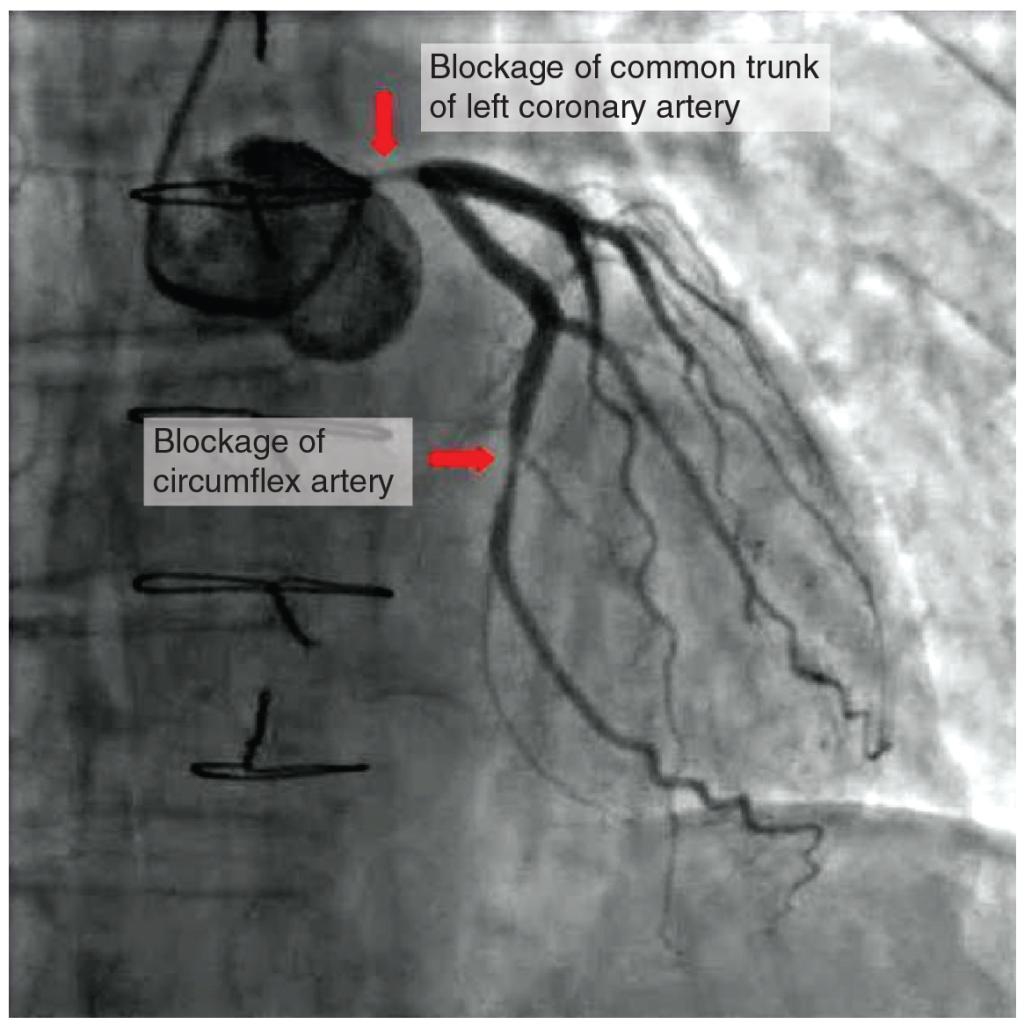

Coronary artery disease is the leading cause of death worldwide. It occurs when the buildup of plaque—a fatty material including cholesterol, connective tissue, macrophages, and some smooth muscle cells—within the walls of the arteries obstructs the flow of blood and decreases the flexibility or compliance of the vessels. This condition is called atherosclerosis, a hardening of the arteries that involves the accumulation of plaque. As the coronary blood vessels become occluded, the flow of blood to the tissues will be restricted, a condition called ischemia that causes the cells to receive insufficient amounts of oxygen, called hypoxia. Figure 19.1.15 shows the blockage of coronary arteries highlighted by the injection of dye. Some individuals with coronary artery disease report pain radiating from the chest called angina pectoris, but others remain asymptomatic. If untreated, coronary artery disease can lead to MI or a heart attack.

This photo shows a blockage in the coronary artery and in the circumflex artery.

Figure 19.1.15 – Atherosclerotic Coronary Arteries: In this coronary angiogram (X-ray), the dye makes visible two occluded coronary arteries. Such blockages can lead to decreased blood flow (ischemia) and insufficient oxygen (hypoxia) delivered to the cardiac tissues. If uncorrected, this can lead to cardiac muscle death (myocardial infarction).